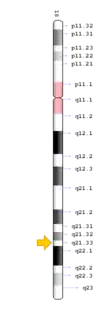

TCIRG1 mutation

The TCIRG1 gene is present in chromosome locus 11q13, which encodes for the a3 subunit of vacuolar H+ ATPase (V-ATPase) that is unique to osteoclasts.[12] The a3 subunit is responsible in anchoring the vacuolar proton pump to the ruffled membrane of osteoclasts.[9] The V-ATPase is important in mediating the transport of hydrogen ions into the resorption lacunae, which is a pit on the bone surface enclosed by the osteoclast for bone resorption. The accumulation of ions in the lacuna facilitates the decomposition of hydroxyapatite crystals by creating an acidic environment, resulting in bone resorption.[12]